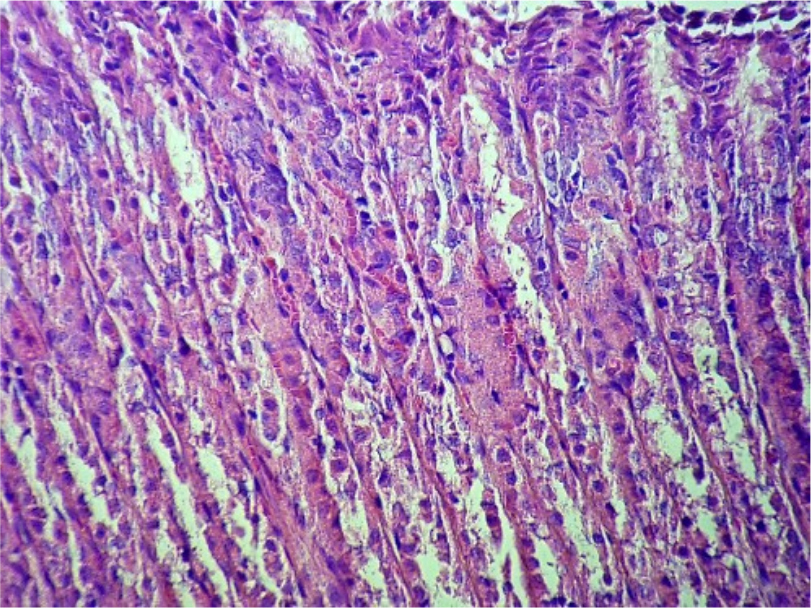

При проведении патоморфологического исследования у животных из второй группы на 6-й было замечено, что слизистая оболочка представлена складками, мышечная оболочка имеет типичное строение. На поверхности слизистой очагово присутствует зернисто-гомогенная масса, состоящая из тотально слущенного поверхностного эпителия, смешанного с большим количеством слизи, а также мелкими нитевидными фрагментами, предположительно растительного корма (Рис. 6). Некоторые участки слизистой в боковой области складок покрыты утолщенным слоем слизи в состоянии отторжения от эпителия. Железы желудка сохранены, содержат большое количество слизистых экзокриноцитов, что придает железам пенистость. Железы за счет развития в них слизистых экзокриноцитов имеют широкие просветы. Также стенка желез выстлана большим количеством париетальных экзокриноцитов.

Рис. 6. Слущенный поверхностный эпителий. Ув. ×100

Между железами микроциркуляторное русло в состоянии стаза, повсеместно собственно-слизистый слой инфильтрирован лимфоцитами (Рис. 7)

Рис. 7. Инфильтрация слизистой желудка лимфоцитами. Ув. ×400

У животных из второй группы на 6-й день по сравнению с животными из первой группы фокусы некроза отсутствуют, деструкция подслизистой основы не выявлена. Присутствует тотальное слущивание поверхностного эпителия.